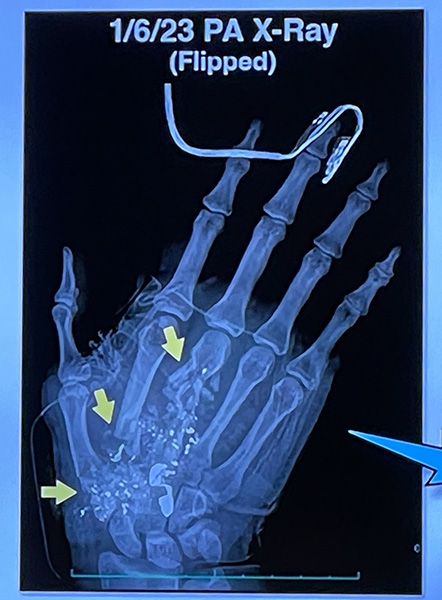

Dr. Romney Andersen is an orthopedic surgeon who began treating Miss Zwerner the day after the shooting. He said she had a “devastating hand injury with a significant amount of bone fractures as well as a number of soft tissue injuries.”

Dr. Andersen said that on a scale of one to ten this was “a ten-type injury,” similar to injuries he had treated in war zones in Iraq and Afghanistan. He showed the jury X-rays of Miss Zwerner’s hand, which was filled with bullet fragments and pieces of her shattered bones.

X-ray of plaintiff’s hand injuries

Dr. Andersen described how damage to Miss Zwerner’s tendons and nerves would severely impact her use of her hand.